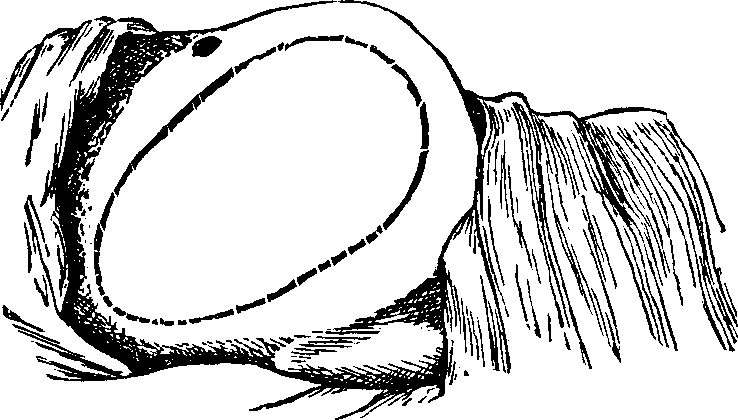

Malformation of the Vagina. Retention of the menses may result from malformation of the vaginal canal, which sometimes terminates before it reaches the womb, being simply a short, closed sac. If the uterus and ovaries are perfect, all the feminine characteristics are manifest, and a vaginal exploration discloses the nature of the difficulty. If, however, the sides of this passage adhere in consequence of previous inflammation, they may be carefully separated by a surgical operation, and this function restored.

Absence or Malformation of the Womb. The uterus may be deformed or entirely absent, and yet there be an inclination, or symptoms indicative of an effort, to establish this function. The individual may be delicate in organization, graceful in bearing, refined and attractive in all feminine ways, and yet this organ may be so defective as to preclude the establishment of the menstrual function. Sometimes there is merely an occlusion of the mouth of the uterus, the perforation of which removes all difficulty. In others, the neck of the womb is filled with a morbid growth, or the walls of its canal are adherent, as the result of inflammation, and may be separated by a small silver or ivory probe, and the menses be thus liberated.

Imperforate Hymen. The hymen is a circular, or semilunar membrane, which imperfectly closes the outer orifice of the vagina in the virgin. When of a semilunar shape, it usually occupies the lower or posterior portion of the canal, leaving an opening in the upper or anterior portion, varying from the size of a quill to that of a thimble, through which the menstrual fluid exudes. This membrane is usually ruptured and destroyed by the first sexual intercourse, and, hence, its presence has been considered evidence of virginity. Its absence, however, must not be considered a conclusive evidence of sexual intercourse, for, as Dr. Dunglison says, "many circumstances of an innocent character may occasion a rupture or destruction of this membrane. It is often absent in children soon after birth; while it may remain entire [pg 688]after copulation. Hence, the presence of the hymen does not absolutely prove virginity; nor does its absence prove incontinence, although its presence would be prima facie evidence of continence."

Sometimes this membrane, when not imperforate, is so thick and strong as to render sexual intercourse impossible, and requires a cutting operation to open the vagina. Several such cases have been operated upon at the Invalids' Hotel and Surgical Institute.

It occasionally happens that the hymen is entire, or imperforate, at birth. This may not be discovered before puberty. But when this period arrives and the menstrual discharge takes place into the vagina, the female will suffer from the retention and accumulation of this secretion, and ultimately a tumor or a protrusion of the membrane which closes the vagina will occur, giving rise to severe pain and other serious symptoms. The retained menstrual fluid, increasing in quantity at every monthly period, dilates the womb as well as the vagina, and even the Fallopian tubes become distended, presenting at length an urgent necessity for relief.

Treatment. This condition admits of relief only by operative surgery. The operation consists in dividing the hymen by a crucial incision, thus allowing the accumulated fluid to be discharged, after which the vagina is cleansed by syringing it with warm water.

In the obstructive variety of dysmenorrhea, some organic impediment hinders the exit of the menstrual blood from the uterus, which, consequently, becomes distended and painful. The pain may be constant, but is most acute when the uterus makes spasmodic efforts to discharge the menstrual blood. If these efforts prove successful, there is an interval of relief. Flexion or version of the womb may produce partial occlusion of the canal of the neck of the uterus, thus preventing the free flow of the menstrual fluid through it. Tumors located in the body or neck of the uterus often cause obstruction to the free discharge of the menses. Imperforate hymen and vaginal stricture also sometimes cause obstruction and give rise to painful menstruation. As these several abnormal conditions and diseases will be treated of elsewhere in this volume, we omit their further consideration here.

Partial adhesion of the walls of the neck of the womb may result from inflammation of the mucous lining, and prevent a free and easy exit of the menstrual fluid. In many cases, the contracted and narrowed condition of the canal of the cervix seems to be a congenital deformity, for we can trace it to no perceptible cause. It is also true that contraction and partial, or even complete, stricture of the cervix, or neck of the womb, often results from the improper application of strong caustics to this passage by incompetent and ignorant surgeons. Every person has observed the contraction of tissue caused by a severe burn, which often produces such a distortion of the injured part as to disfigure the body for life. A similar result is produced when the neck of the womb is burned with strong caustics. The tissues are destroyed, and, as the parts heal, the deeper-seated tissues firmly contract, forming a hard, unyielding cicatrix, thus constricting the [pg 695]neck of the womb, through which the menses pass into the vagina.